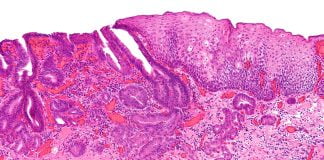

Principalele anomalii de tranzit intestinal

Ce se intelege prin anomalii de tranzit intestinal? Insusi cuvantul anomalie se refera la un defect, la ceea ce se abate de la normal....